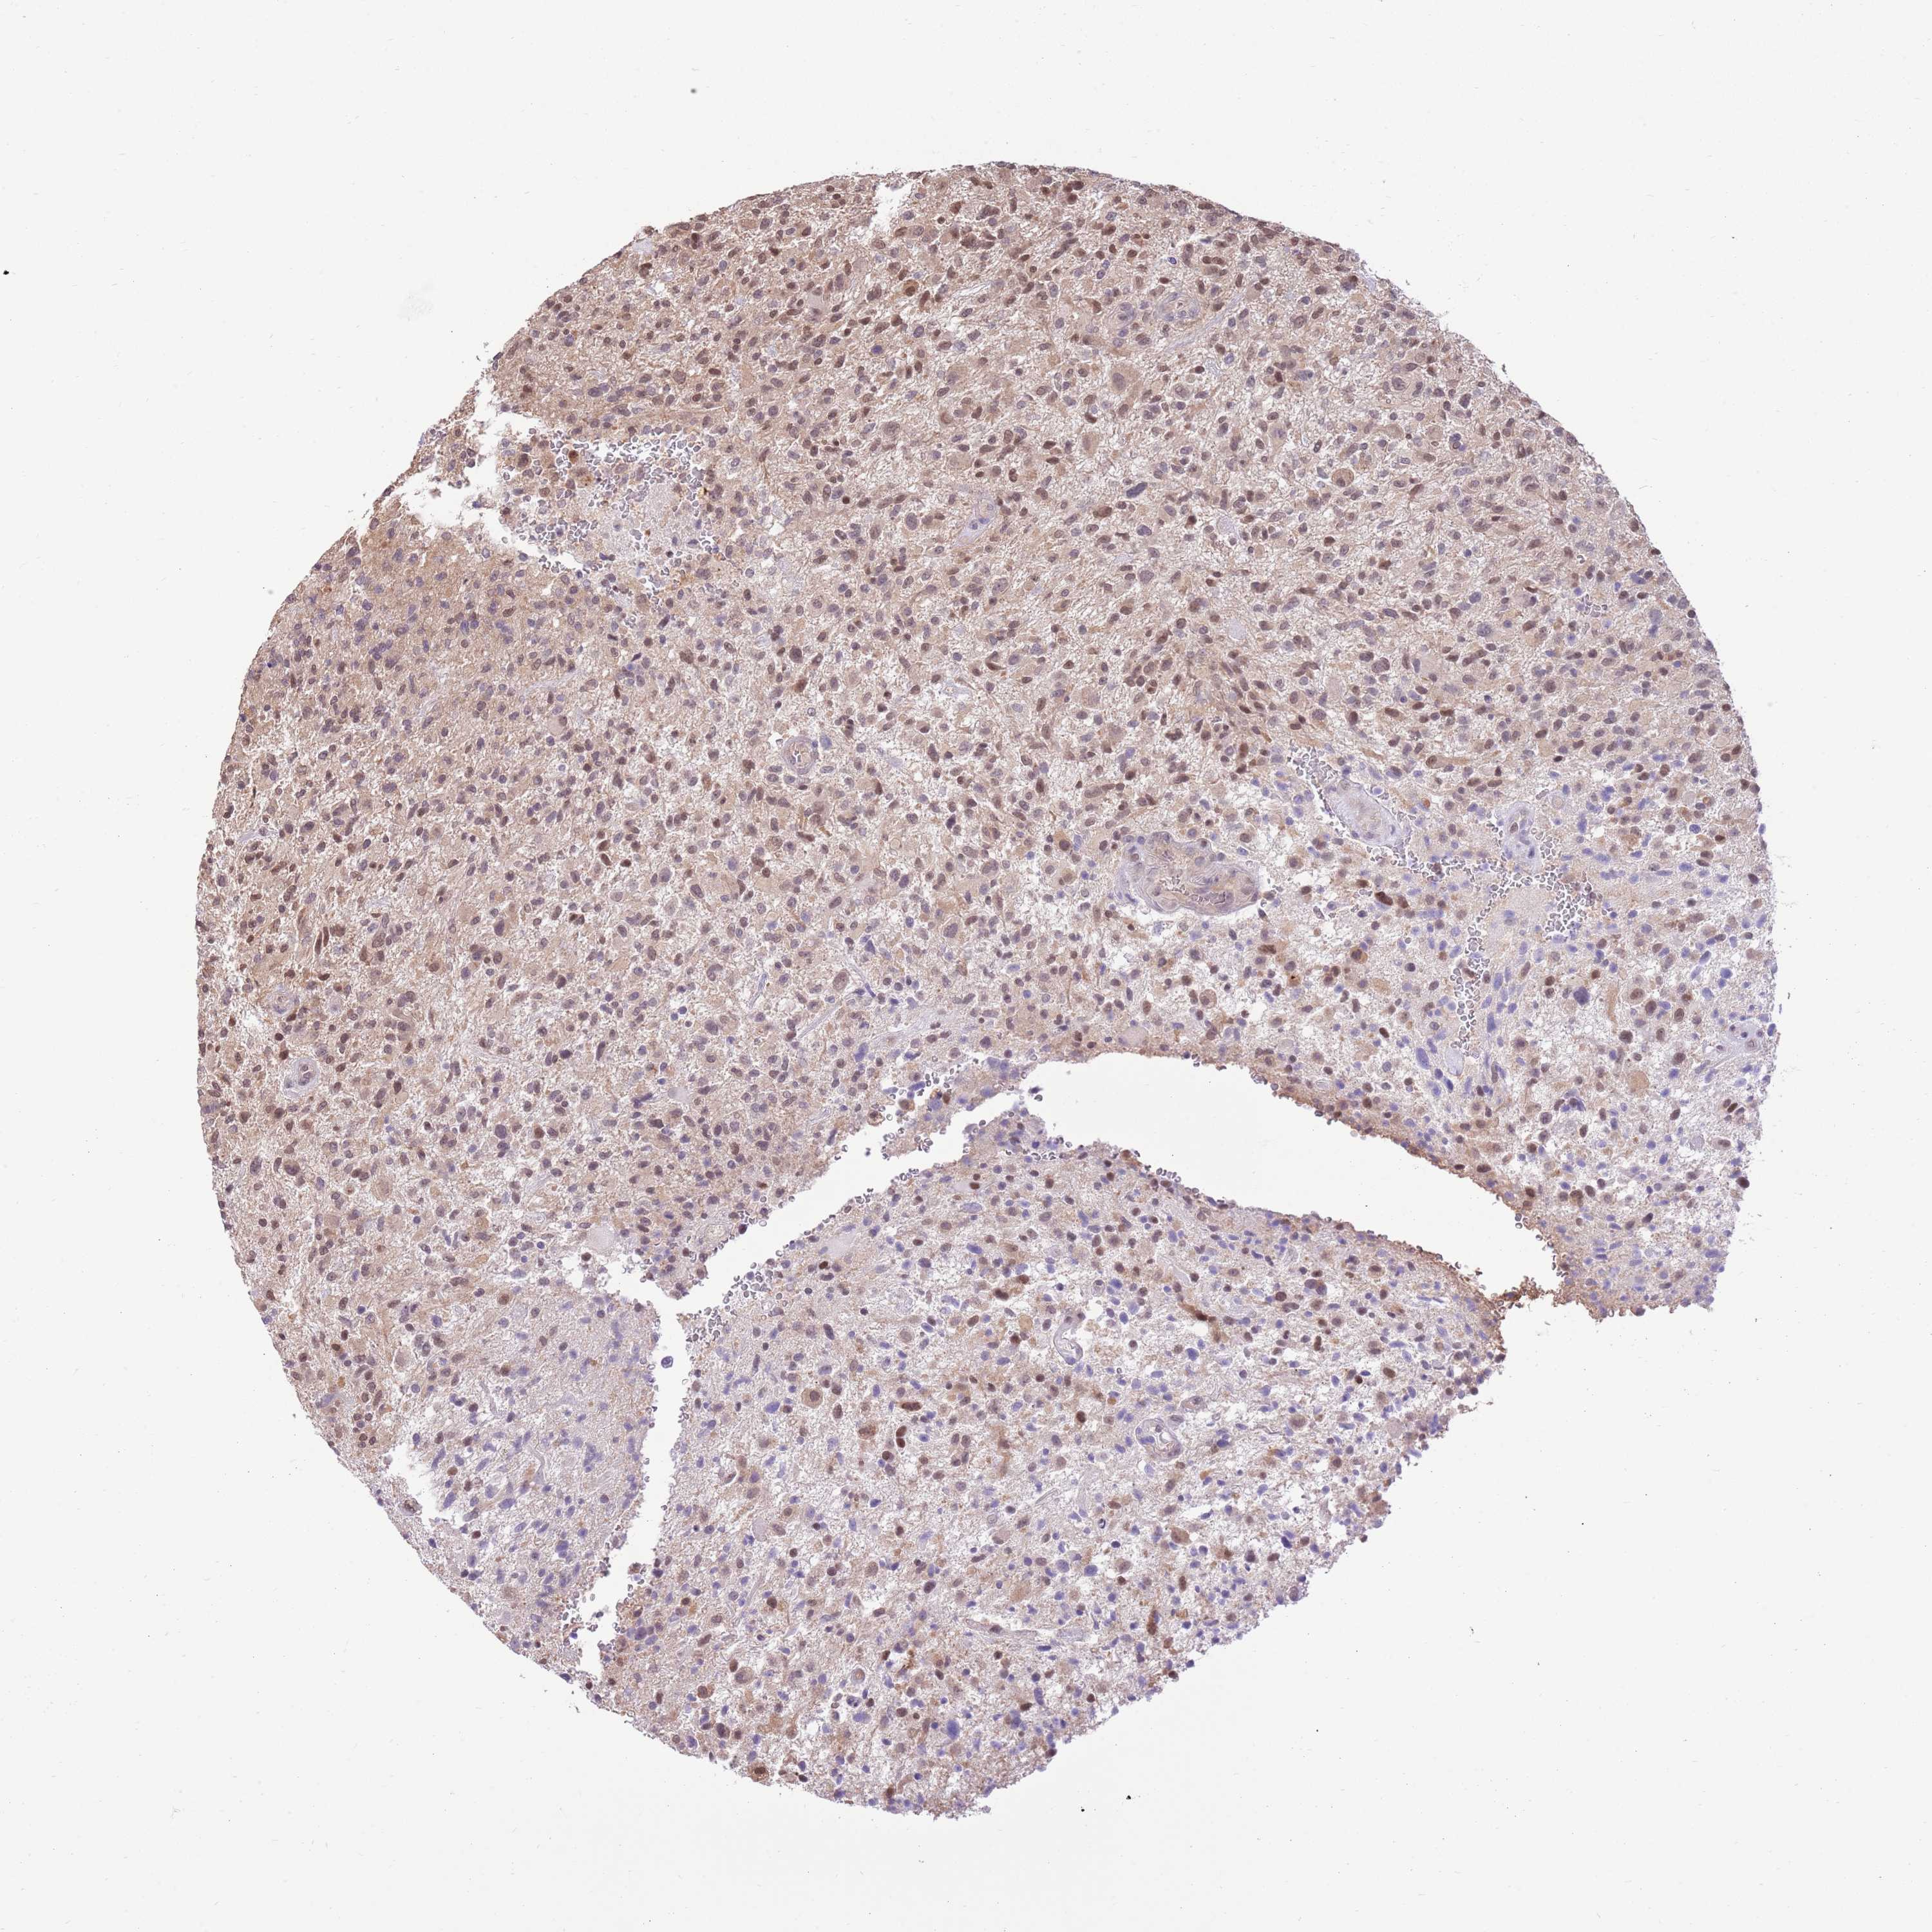

GLIOMA - Protein expressioni

A mouse-over function shows sample information and annotation data. Click on an image to view it in a full screen mode. Samples can be filtered based on level of antibody staining by selecting one or several of the following categories: high, medium, low and not detected. The assay and annotation is described here.

Note that samples used for immunohistochemistry by the Human Protein Atlas do not correspond to samples in the TCGA dataset.

Antibody stainingi

Antibody staining in the annotated cell types in the current human tissue is reported as not detected, low, medium, or high, based on conventional immunohistochemistry profiling in selected tissues. This score is based on the combination of the staining intensity and fraction of stained cells.

Each image is clickable and will lead to virtual microscopy that enables deeper exploration of all samples and also displays staining intensity scores, fraction scores and subcellular localization as well as patient and tissue information for each sample.

Antibody HPA047108

Antibody HPA050628

Staining

High

Medium

Low

Not detected

Intensity

Strong

Moderate

Weak

Negative

Quantity

>75%

75%-25%

<25%

None

Location

Nuclear

Cytoplasmic/membranous

Cytoplasmic/membranous,nuclear

Glioma, malignant, High grade

Glioma, malignant, Low grade